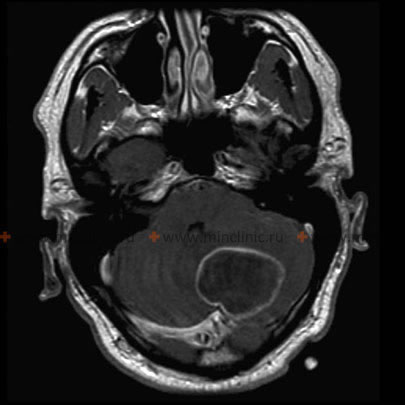

მაგნიტურ-რეზონანსული ტომოგრაფია ტარდება თავის ტვინის აბსცესის ეჭვზე.

- მრტ არის სასურველი გამოსახულების მეთოდი ტვინის აბსცესების დიაგნოსტიკისთვის.

CT და MRI ტომოგრაფია |

ნაკლებად გამიჯნული ანთება | CT: სქელი რგოლის ფორმის გამოკვეთა MRI: T1 ჰიპოინტენსიური, T2 ჰიპერინტენსიური |

გარსს შემოვლებული ნეოვასკულარული რეტიკულარული ქსელი | CT: თხელი რგოლის ფორმის გამოკვეთა MRI: T1 ჰიპოინტენსიური — შეშუპება/ცენტრი, ჰიპერინტენსიური — კაფსულა, T2 ჰიპერინტენსიური — შეშუპება, კაფსულა და ცენტრალურად შეზღუდული დიფუზია |